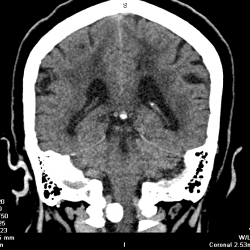

Мужчина.Жалобы на шаткость походки , головокружение.Заболел около 10 дней назад, когда появились вышеуказанные симптомы..А анамнезе около 2-х лет назад-подобное состояние, которое было...